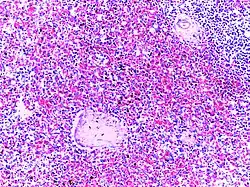

![]() | Follicular lymphoma | Micrograph showing a small B-cell lymphoma compatible with follicular lymphoma. H&E stain. | Category: Histopathology of follicular lymphoma | Follicular lymphoma |